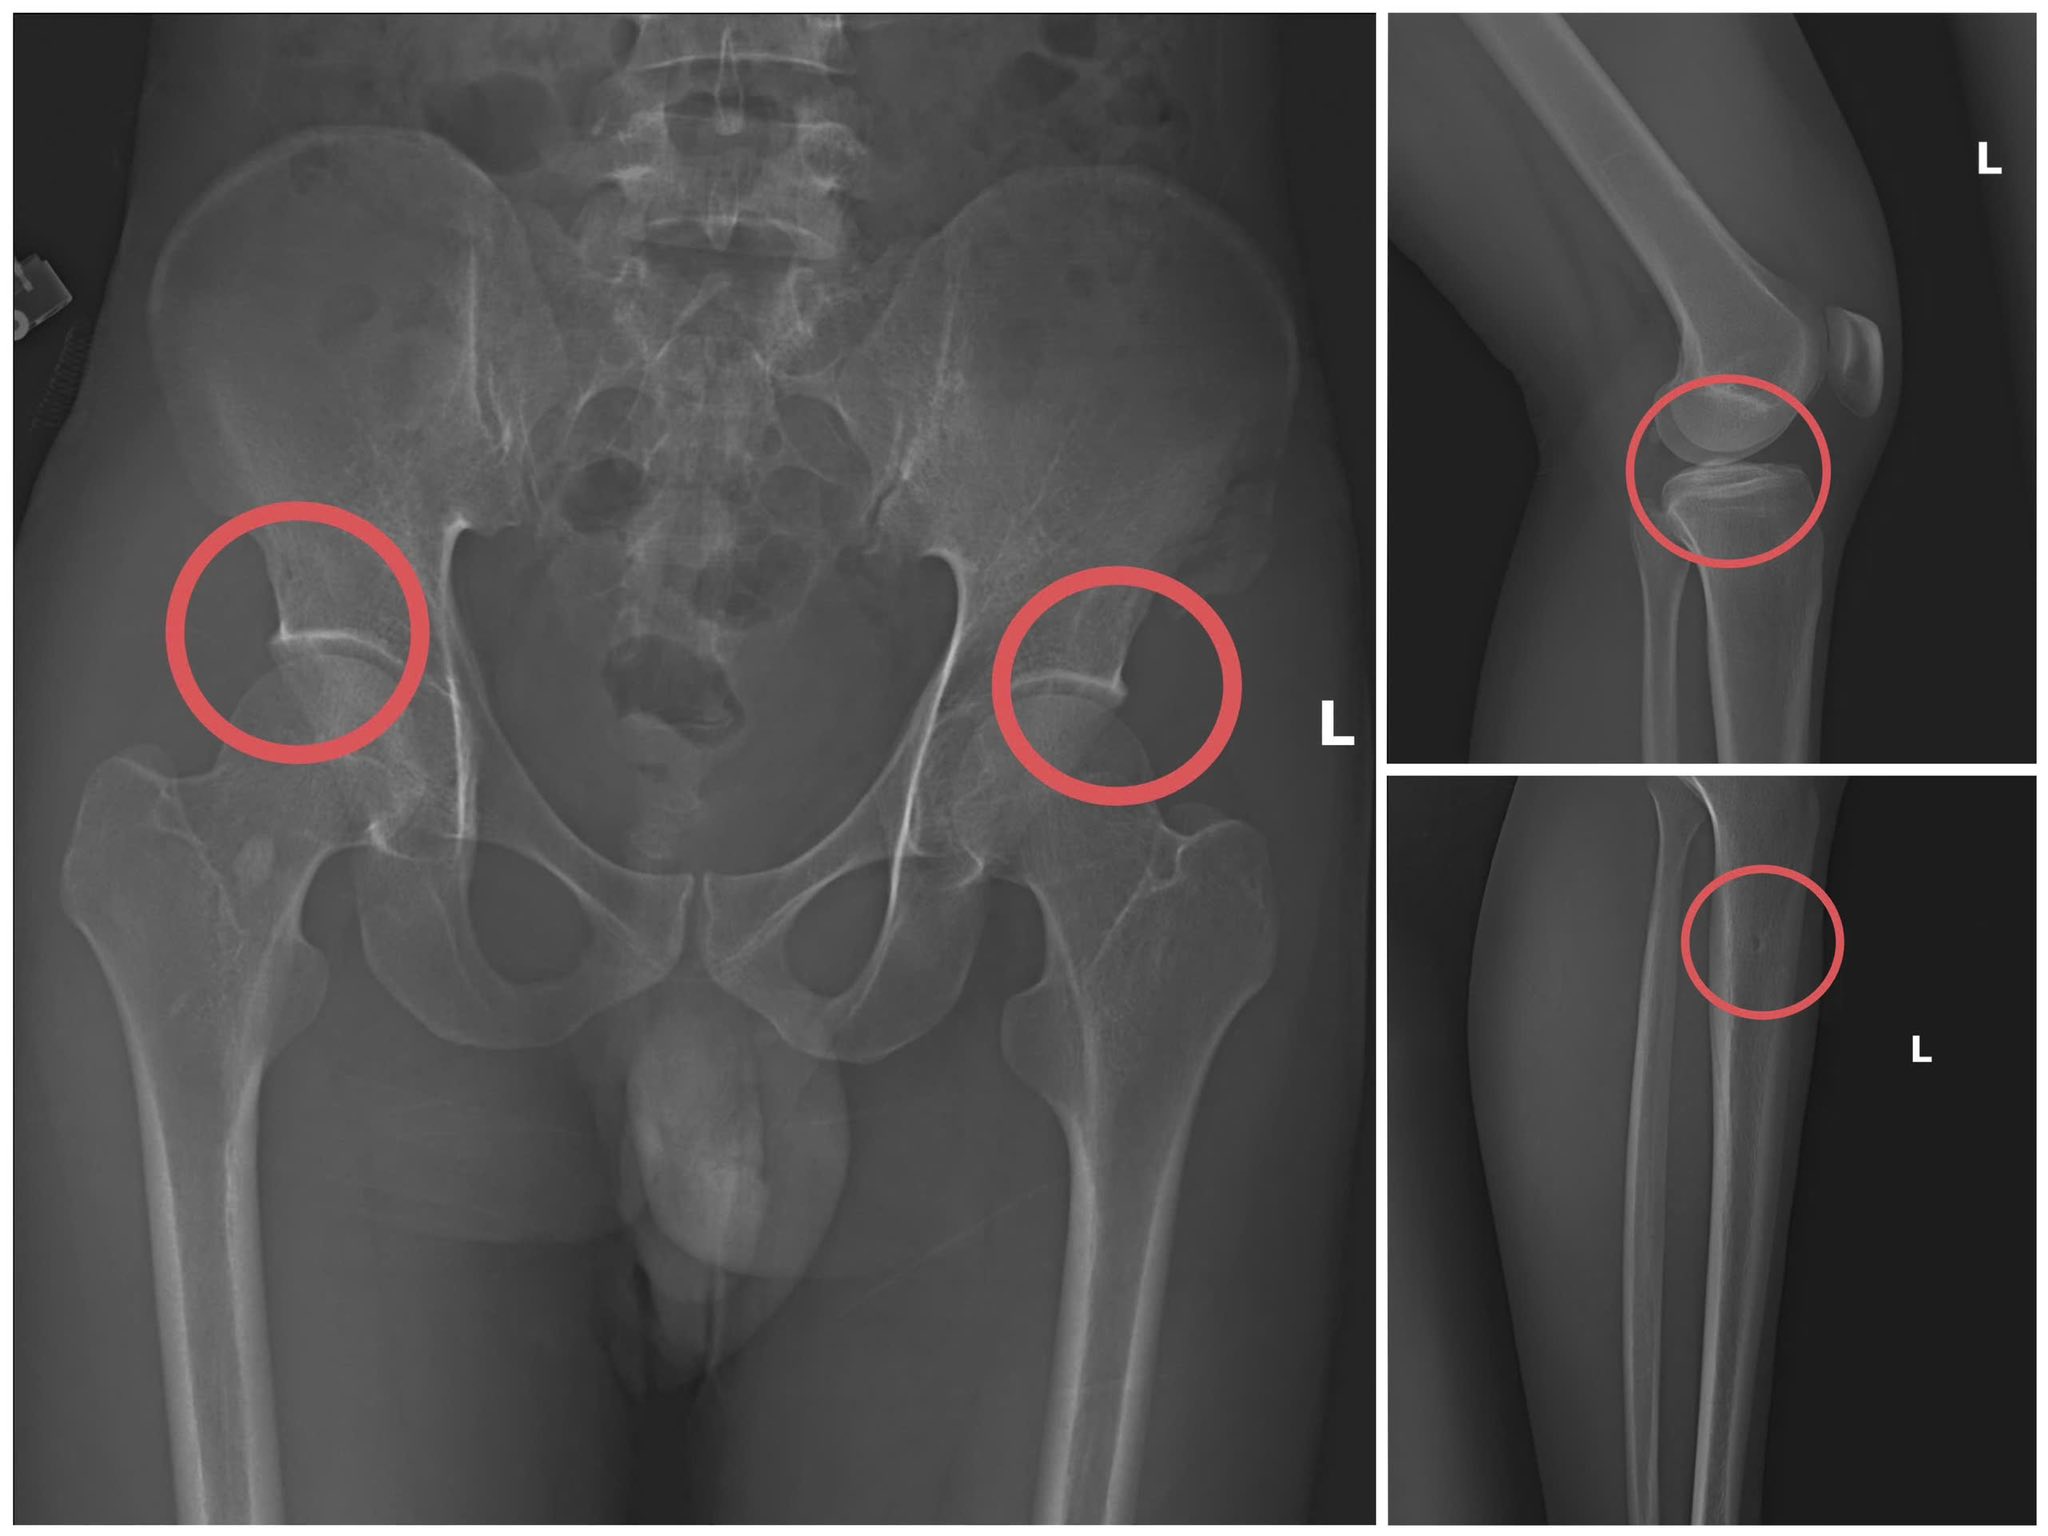

Tạ Minh Châu trực tiếp thực hiện hành vi tiêm thuốc mê, dùng búa đinh tác động vào xương người mua bảo hiểm, tạo nên các vết nứt xương tương tự tai nạn thật. Khi thương tích đã tạo xong, Châu tiếp tục hướng dẫn các đối tượng dựng hiện trường giả như điện giật ngã, trượt chân ngã suối nhằm hợp thức hóa bệnh án và hoàn thiện hồ sơ yêu cầu chi trả.

Các đối tượng dùng búa đập vào xương tạo ra thương tích để chiếm đoạt tiền của các công ty bảo hiểm. Ảnh: Công an cung cấp |

Theo cơ quan công an, đây là thủ đoạn vô nhân tính, coi thường sức khỏe, tính mạng của người tham gia. Đối tượng đã tính toán kỹ để gây thương tích đúng vị trí có mức chi trả cao, khiến các công ty bảo hiểm khó phát hiện dấu hiệu gian dối.